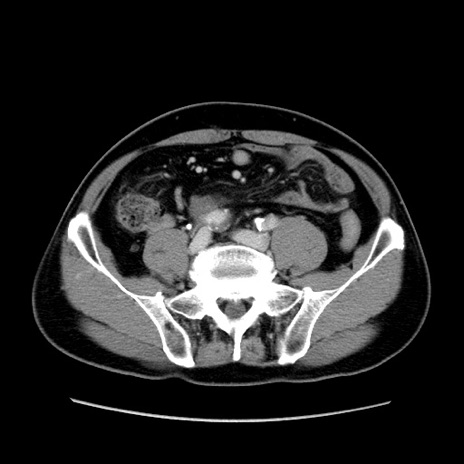

症例34(横断像)

【症例】60歳代 男性

【主訴】右鼠径部膨隆

【現病歴】1年程前より右鼠径部膨隆あり。自己にて還納可能だったため放置していた。3時間前より右鼠径部の脱出を認め、還納困難となり受診。

【既往歴】高血圧

【身体所見】右鼠径部に小児頭大の膨隆あり。弾性硬であり、用手還納は困難。左鼠径部にも膨隆を認める。脱出はなし。

【データ】WBC 15500、CRP 測定なし